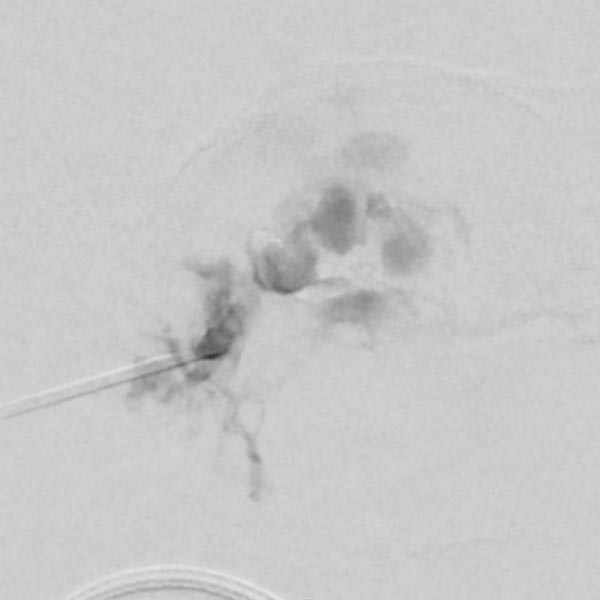

In view of the hypervascularization and the extension into the orbit, a preoperative embolization was performed with ethylene-vinyl alcohol copolymer in a direct puncture technique. Intraoperative DSA with venous drainage is depicted here.

The X-ray fluoroscopy image shows the embolic agent within the vessels in black (radiopaque). The perfusion of the infantile hemangioma was super-selectively reduced.